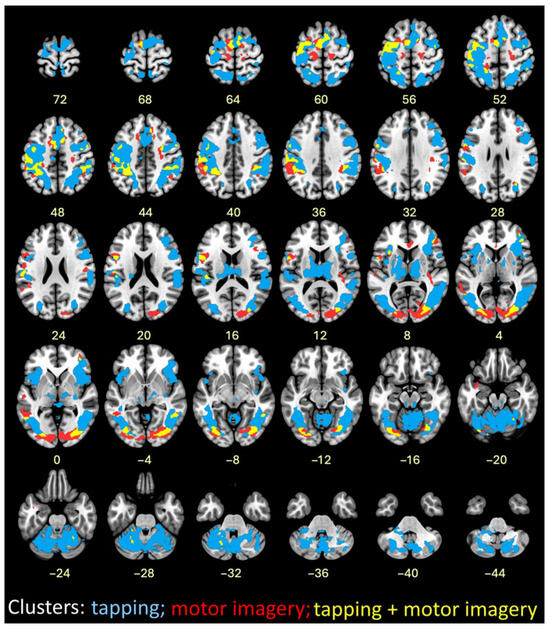

Using an event-related analysis, successful motor imagery events (i.e., true ITAP TRs) were compared to all other events in Runs 3 and 4, as shown in Figure 5 and Table 2. The most robust activations were located in visual, frontal, supplementary, and premotor brain regions. Cerebellar regions were also activated, mainly on the left side.

Figure 5.

(left) Contrasts between successful motor imagery vs. all other trials. (right) Covariates of Δ RMSE tapping accuracy (improvements) with successful motor imagery; cluster colors reflect correlations between cluster activation level and tapping accuracy improvements. Red = positive correlation; blue = negative correlation; p < 0.001. The left side of the brain is shown on the left. See Methods for cluster thresholds.

3.5. FMRI Successful Imagery Covariates

Successful motor imagery events covaried with individual tapping accuracy improvement scores (Δ RMSE values), as shown in Figure 5 and Table 3. Most covariates were significant and positive at the 1 Hz speed, indicating that larger improvements in tapping accuracy were associated with increasing brain activations during successful motor imagery. These were located in the frontal lobe, insula, parietal lobe, basal ganglia, and cerebellum. One activation, located in the frontal lobe white matter, negatively covaried with improvement at 1 Hz (Figure 5 and Table 3). At 4 Hz, the angular gyrus positively covaried with improvement (Table 3). Visualization of scatterplots indicated strong associations that were not driven by a few individuals (Figure 6 and Table S3). A conjunction analysis showed overlap between tapping and imagery in frontal (including SMA, premotor, and sensorimotor), parietal, visual, and cerebellar regions (Figure 7).

Figure 7.

Image overlay of finger tapping at both speeds combined (blue); successful motor imagery (red); and conjunction of finger tapping and successful motor imagery (yellow).